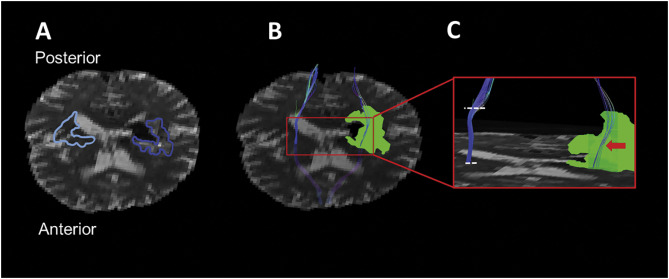

Figure for Peri-Hematoma Corticospinal Tract Integrity in Intracerebral Hemorrhage Patients: A Diffusion-Tensor Imaging Study.

Peri-Hematoma Corticospinal Tract Integrity in Intracerebral Hemorrhage Patients: A Diffusion-Tensor Imaging Study.

Rebecca Mccourt, Ehsan Misaghi, Wei Tu, Mahesh Kate, Laura Gioia, Sarah Treit, Christian Beaulieu, Ken S. Butcher

Journal of the neurological sciences (2021)